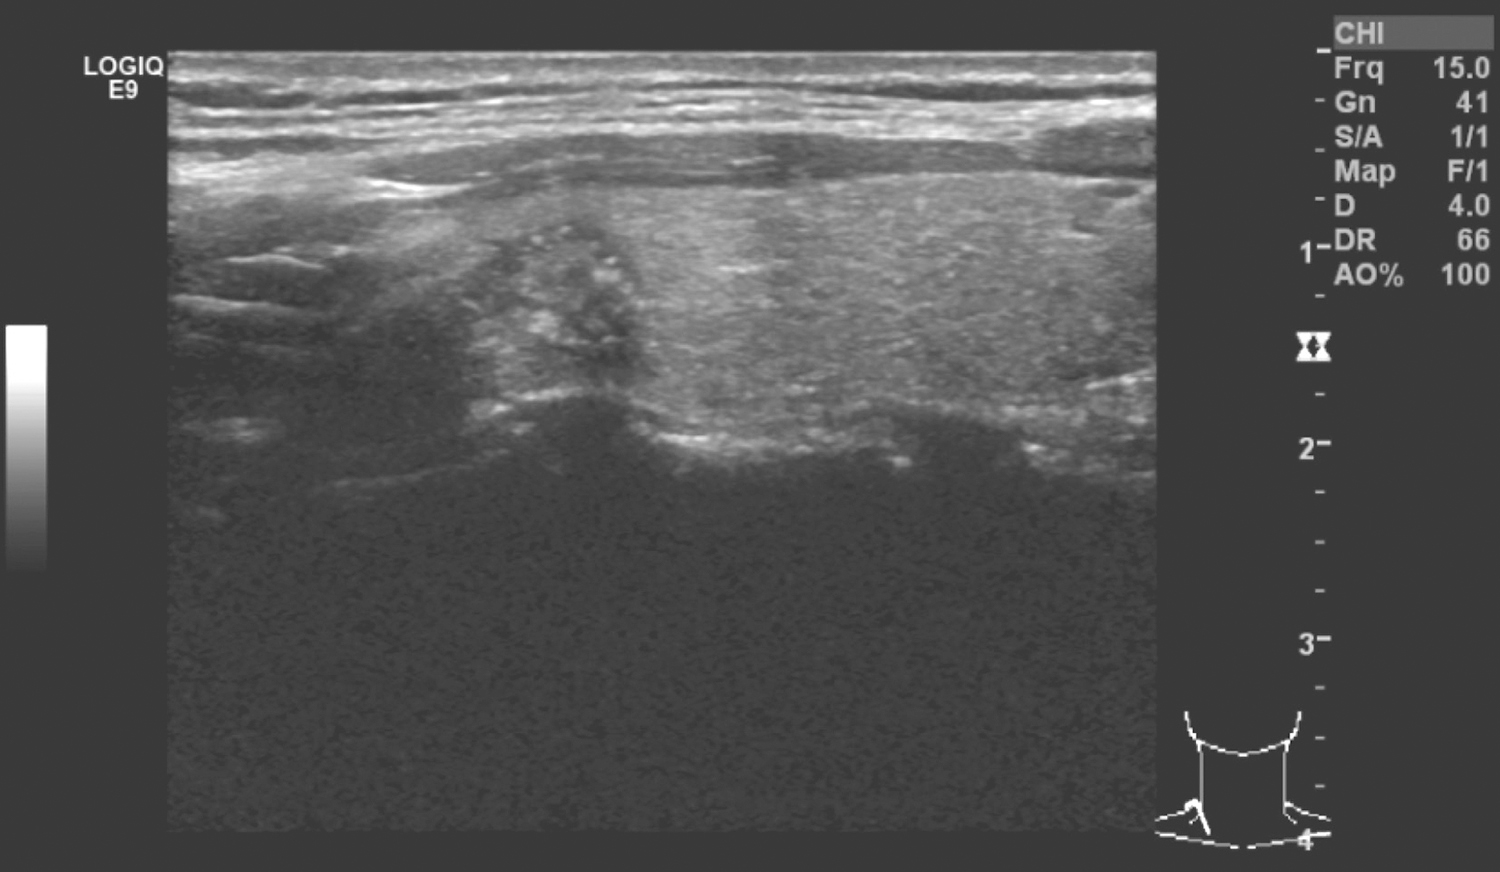

甲状腺右叶上极外侧见低回声结节,约0.7cm×1.0cm,边界不清,内回声不均匀(图1);余腺体未见明确结节及肿物。右颈Ⅲ~Ⅵ区见多发低回声病变,较大者位于4区,约1.3cm×2.9cm,边界不清,内见无回声区。余颈部未见明确可疑肿大淋巴结。

图1 颈部超声示甲状腺右叶上极外侧见低回声结节

超声诊断:

(1)甲状腺右叶上极外侧实性病变,恶性。

(2)右颈Ⅲ~Ⅵ区多发淋巴结肿大,符合转移瘤。